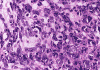

At low power magnification (Panel A and B), the tumor seems to have two distinct components. The first is a highly cellular, basophilic, background stroma. The second is islands of well-demarcated, pale bluish chondroid, hypocellular areas reminiscent of hyaline cartilage. Together, these two components impart a so-called "white clouds in blue sky" histologic appearance. At medium- and high power magnification (Panel C and D), the lacuna in the chondroid areas are well appreciated which helps to confirm the cartilaginous nature of these pale islands. Please note the impressive nuclear pleomorphism in the neoplastic chondrocytes (Panel D).

The basophilic background is composed of tightly packed, undifferentiated spindle cells without significant deposition of collagen fibers in between (Panel E). Panels  F, G, and H are taken from a different area of the tumor and were not posted on the question web-page. The pathologic change in these areas are very common among mesenchymal chondrosarcoma and should be looked. These include lobules of highly cellular tumor separated by fibrous connective tissue septa (Panel F) and Prominent tumor vascularity with highly branching vessels which (with a bit of imagination!) resemble deer "antlers" or "staghorns"(Panel G and H). This pattern of vessel distribution is similar to that seen in hemangiopericytoma (an uncommon soft tissue tumor) and is therefore often described as a “hemangiopericytoma-like” vascular pattern. The overall gross and light microscopic features in this case are consistent with a diagnosis of primary extraskeletal mesenchymal chondrosarcoma.